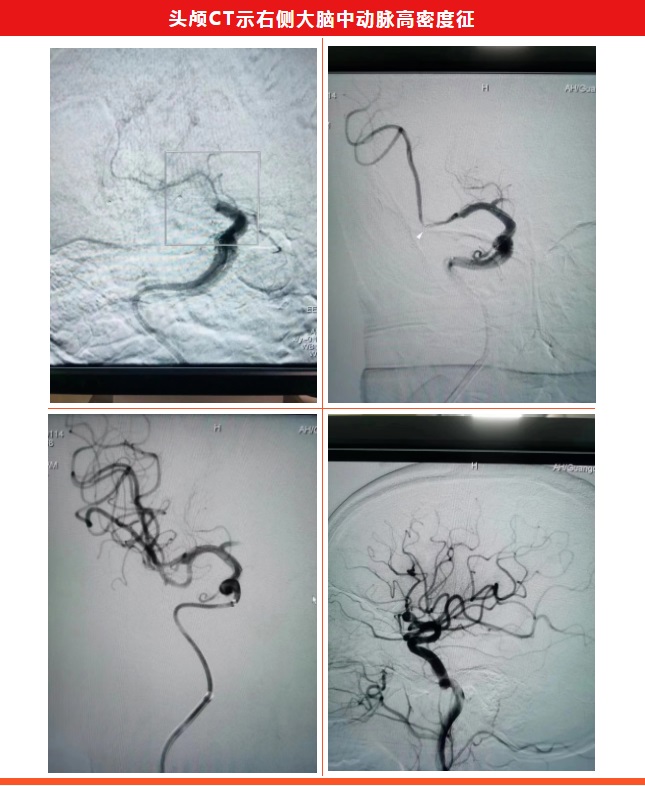

近日,一名57岁男性突发左侧肢体瘫痪伴意识模糊1小时,入住我院神经内科,经过医生细致检查后,评估该患者NIHSS20分,右侧大脑中动脉栓塞,通桥蛟龙4X20支架配合银蛇中间导管抽拉结合,血管再通。

术后第二天,症状较术前明显改善,左侧上下肢可抬离床面,轻度口角歪斜,NIHSS评分3分。

术后第六天,患者右侧上下肢无力完全恢复,NIHSS评分1分。